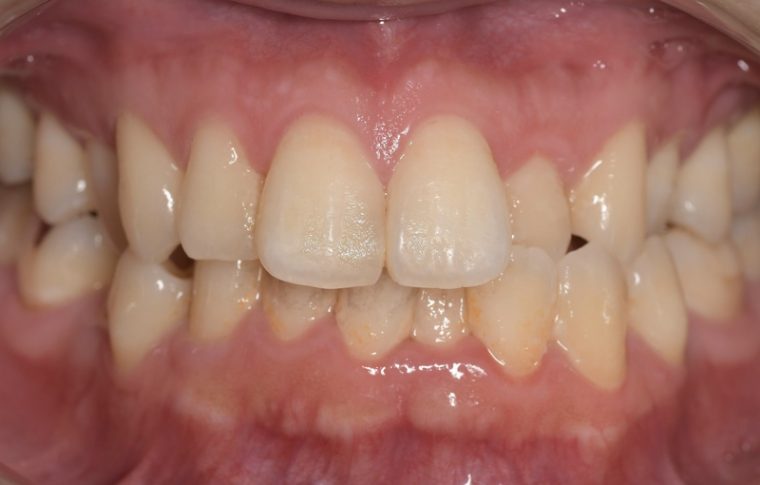

CASE 3

Before

After

基本情報

| 年齢・性別 | 30代・女性 |

| 主訴 | 定期検診 |

| 治療内容 | PMTC |

| 治療期間 | 60分 |

| 治療費 | 5,750円 |

| リスク・副作用 | しみる可能性があります。 |

| 治療方針 | PMTCでステインの除去。 |

| 担当者所見 | ステインが付きやすいため、3カ月毎の定期検診で除去する。 |